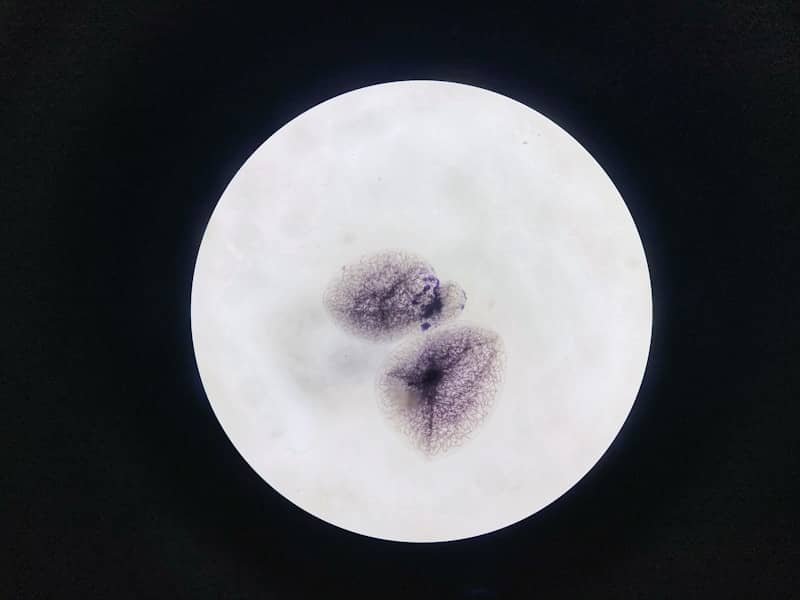

Najčešći znaci su obilan, tanak, sivkasto-bijeli sekret sa neprijatnim mirisom ribe, naročito nakon odnosa, te blaga iritacija ili svrbež. Mnoge žene su asimptomatske, pa infekcija ostane neotkrivena. Dijagnoza se postavlja prema standardnim kriterijima: vaginalni pH > 4,5, obiljan tanak sivkasto-bijeli sekret, prisustvo "Clue" ćelija na mikroskopskom preparatu i pozitivan 'whiff' test.